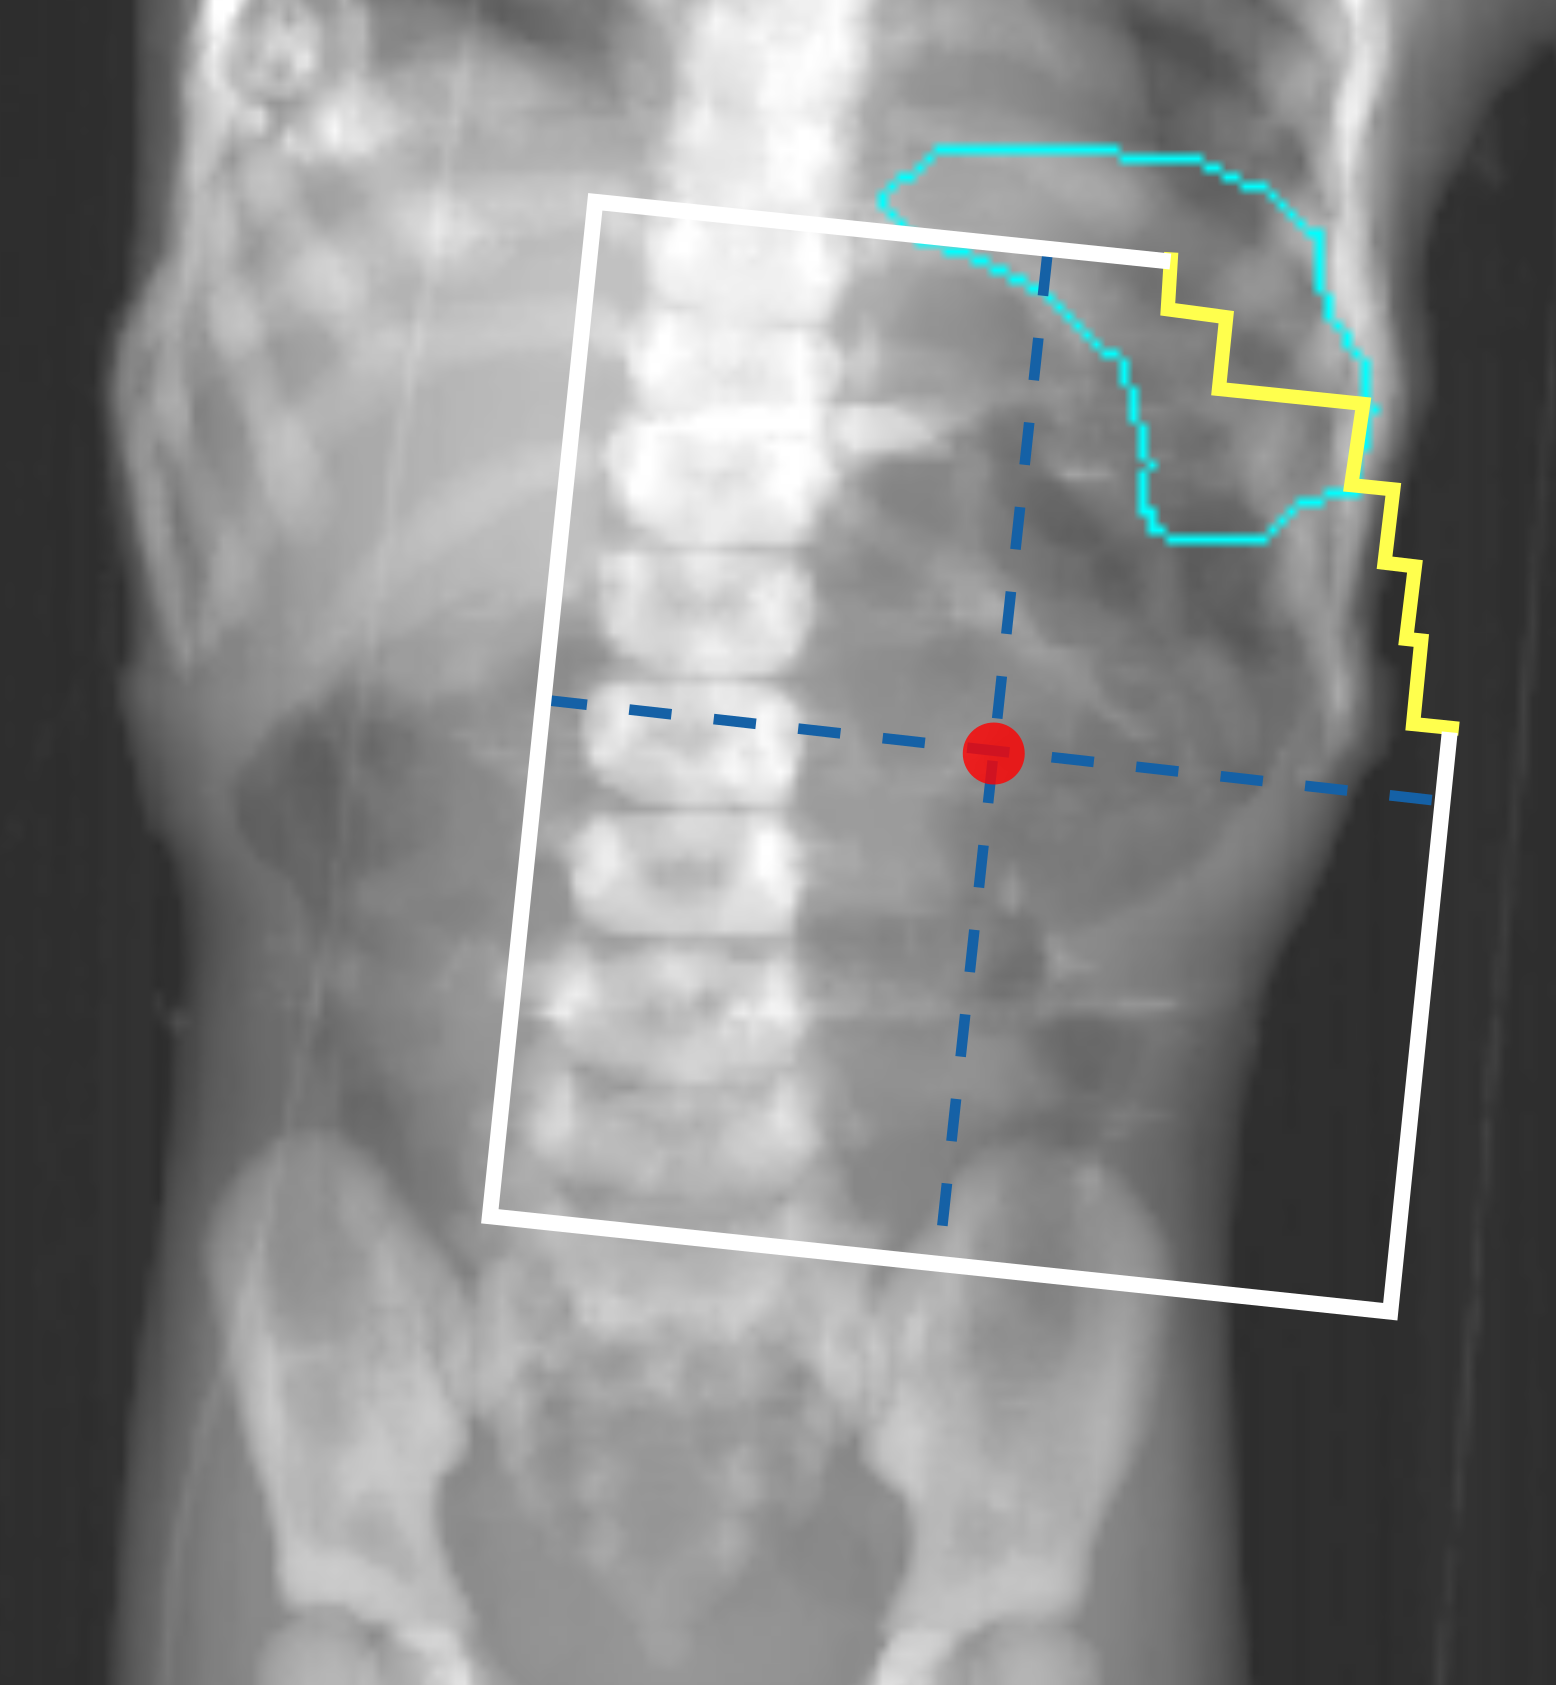

Figures 1(a) and 1(c) illustrate examples of actual historical plans on respective historical radiographs. As can be observed, a typical historical flank irradiation field is a rectangular area, with possible shielding blocks, that is located on the right or on the left flank. Irradiation is done by beams from anterior-posterior (AP) and posterior-anterior (PA) direction. Along right-left (RL), one field border is located at the edge of the patient’s body contour, while the other is located as to include the vertebral column (?). In some cases, blocks are placed to protect OARs from irradiation (Fig. 1(c)). In historical plans the isocenter is positioned in the center of the treatment field that is projected on the coronal plane (Fig. 1) and at the middle of the patient’s AP abdominal diameter.

To generate artificial plans, two reference digitally reconstructed radiographs (DRRs) were considered, randomly selected from the data. One DRR was derived from a CT of a 5-year old female patient without nephrectomy (ref 1 in Fig. 2), and the other was derived from a CT of a 4-year old female patient with nephrectomy of the left kidney (ref 2 in Fig. 2). Upon these two DRRs, boundaries defining the extent of variation for clinically reasonable fields were identified by an experienced pediatric radiation oncologist (B. V. Balgobind) Note that historical clinical guidelines are slightly different from current ones (e.g., currently the iliac crests should be safeguarded, unlike in Fig. 1(c)). Figure 2 shows two examples of landmark locations identifying possible plan variations, on the two reference DRRs. Specifically, given the boundaries of possible isocenter positions and field borders, plans with a rectangular field were generated by sampling uniformly within those boundaries.

For each plan generated, an additional version of that plan including one block was generated as well. A block was simulated as the area in the upper lateral corner enclosed by the border of the rectangular field and a line crossing two randomly sampled endpoints. The endpoints were sampled from two regions roughly covering the start and end points of rib 9 and rib 12 on the DRRs (regions indicated by the green boxes in Fig. 2). This way, a sampled block covered part of the liver (in right-sided plans) or part of the spleen (in left-sided plans). All plans consisted of two opposing and symmetrical beams in AP-PA directions irradiating one side of the abdominal flank. Figures 1(b) and 1(d) illustrate two examples of sampled artificial plans (without or with a block) on respective DRRs.